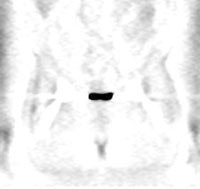

Genitourinary activity: The image below demonstrates activity within the collecting system of a transplanted kidney (black arrows). This should not be mistaken for an abnormality. |

|